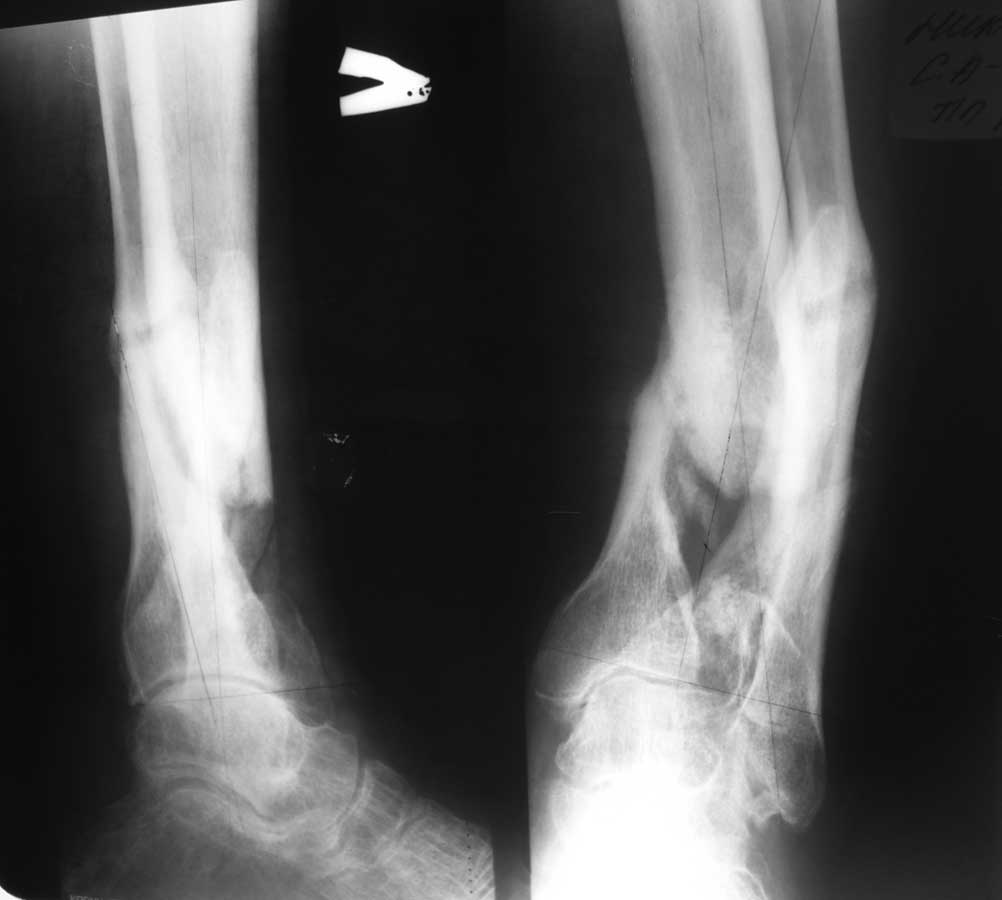

[Ortho] Ложный сустав голени

Уважаемый Александр Николаевич! Вот фото рентгенограмм.